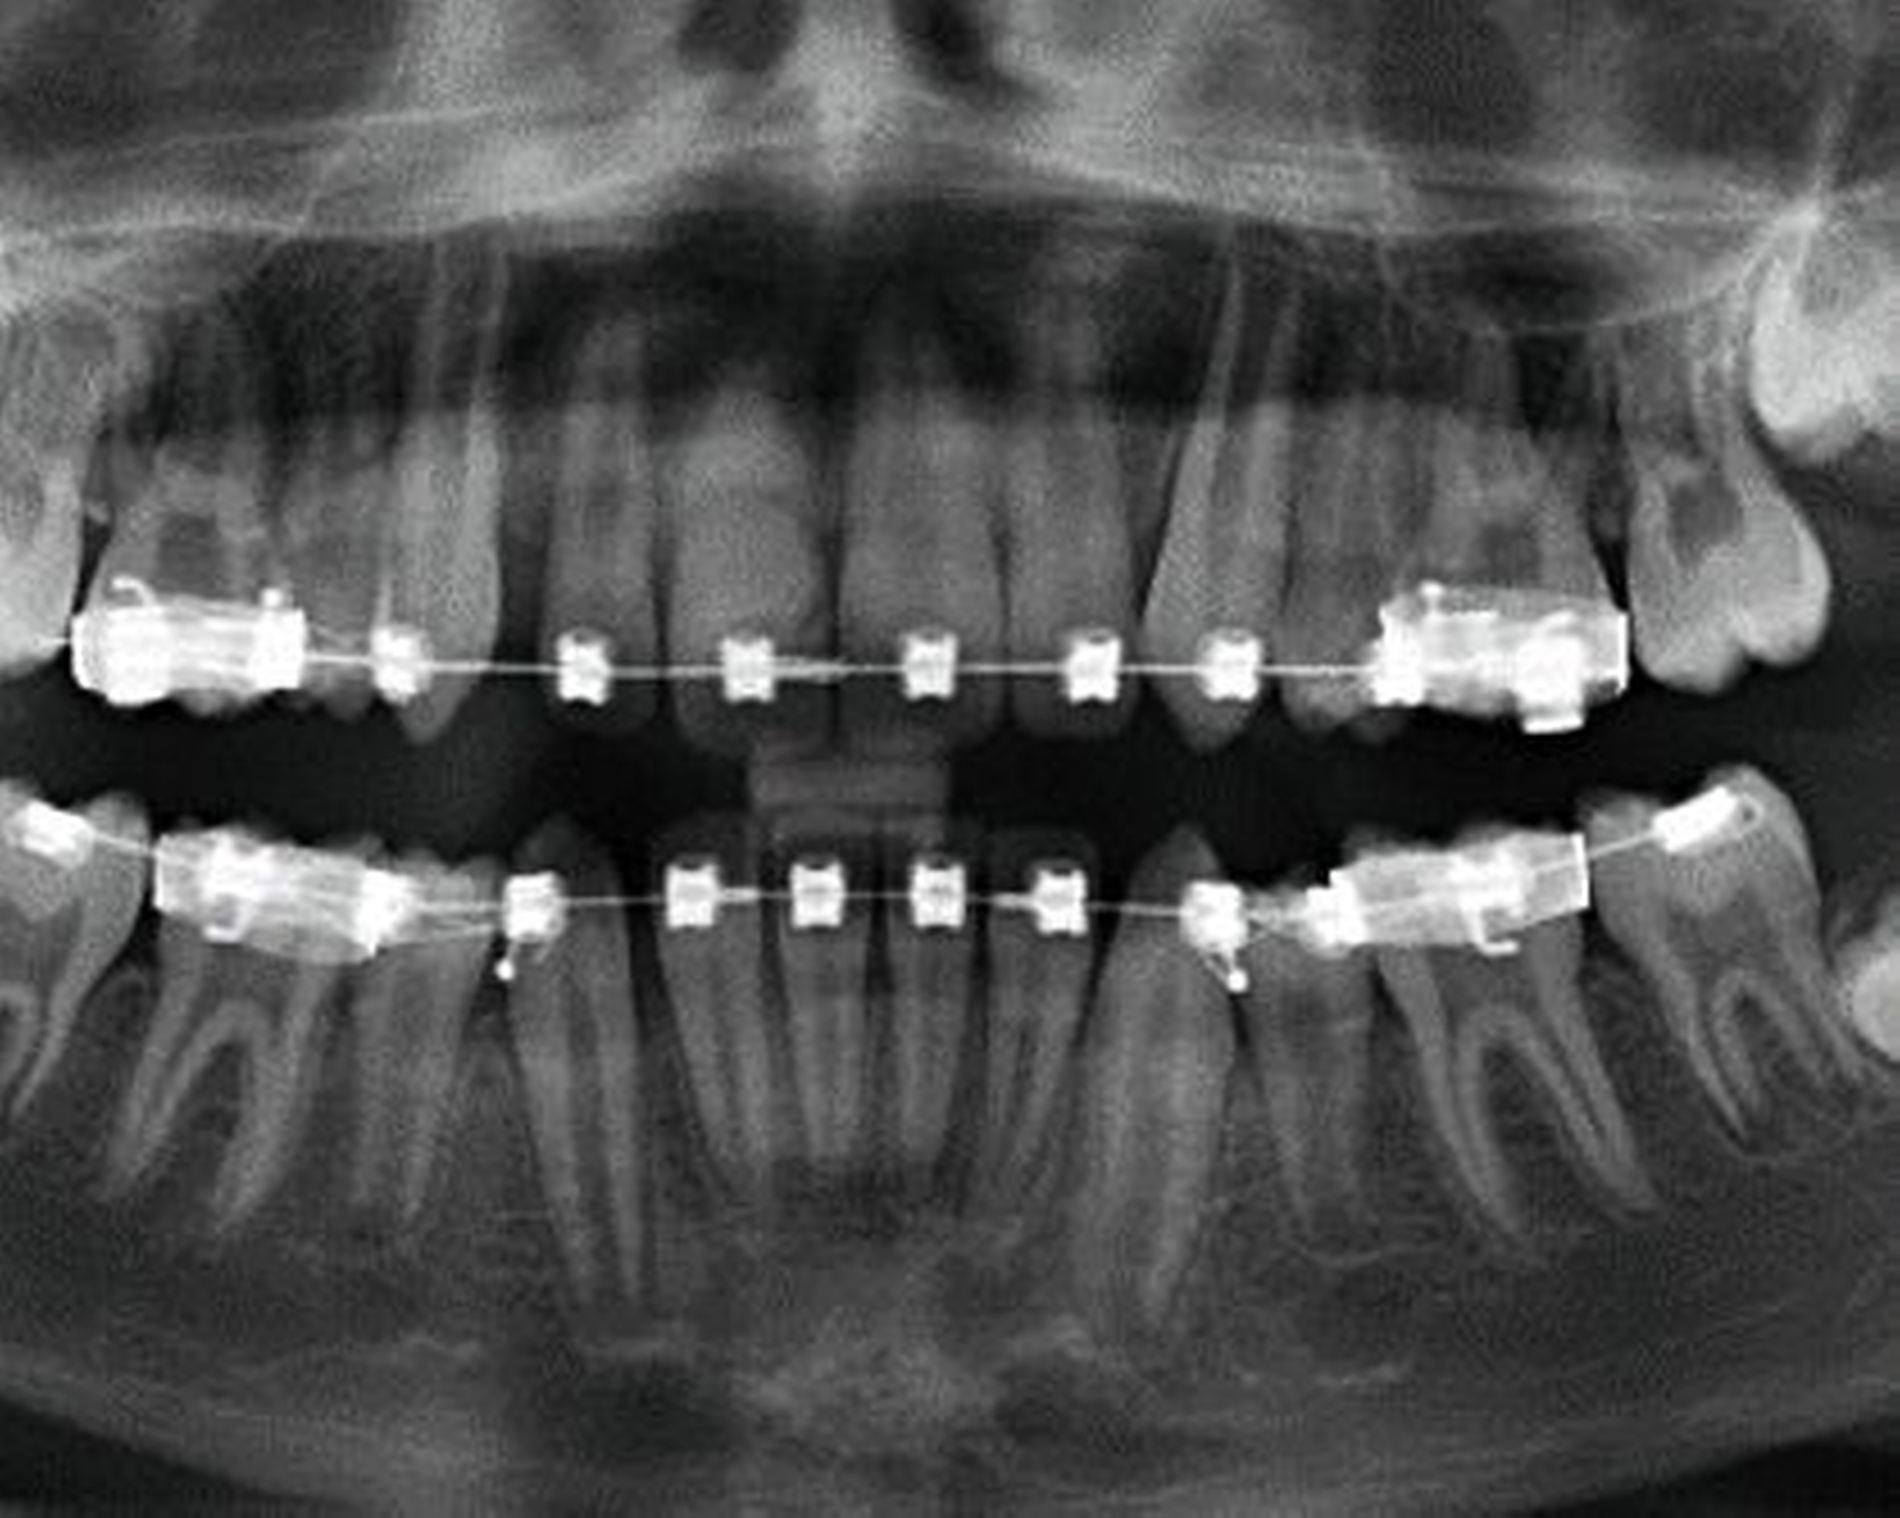

Eine Dekoronation ist eine chirurgische Intervention, die durchgeführt werden kann, wenn aufgrund ausgeprägter Schädigungen der desmodontalen Zellen und der Wurzeloberfläche eine Resorption auftritt. Im Rahmen der klinischen Untersuchung imponiert der betroffene Zahn aufgrund der Ankylose mit einem metallischen (hellen) Klopfschall. Röntgenologisch lassen sich Resorptionslakunen an der Wurzeloberfläche erkennen. Bei progressiver Resorption und Infraposition des betroffenen Zahnes in Relation zur Restdentition kann eine Dekoronation indiziert sein [Malmgren et al., 2015] (Abbildung 2).

Das Ziel der Dekoronation ist es, die klinische Krone unter Belassung der resorbierenden Wurzel zu entfernen, damit der Alveolarknochen aufgrund der Knochenneubildung bei Ersatzresorption erhalten und eine optimale Voraussetzung für spätere Interventionen gegeben werden kann [Malmgren et al., 2006]. Bei Patienten im Wachstum kann die Dekoronation eine sinnvolle Therapieoption darstellen, um den teils erheblichen Knochenverlust in Verbindung mit der chirurgischen Entfernung der ankylosierten Zahnwurzel zu vermeiden (Empfehlung 60).